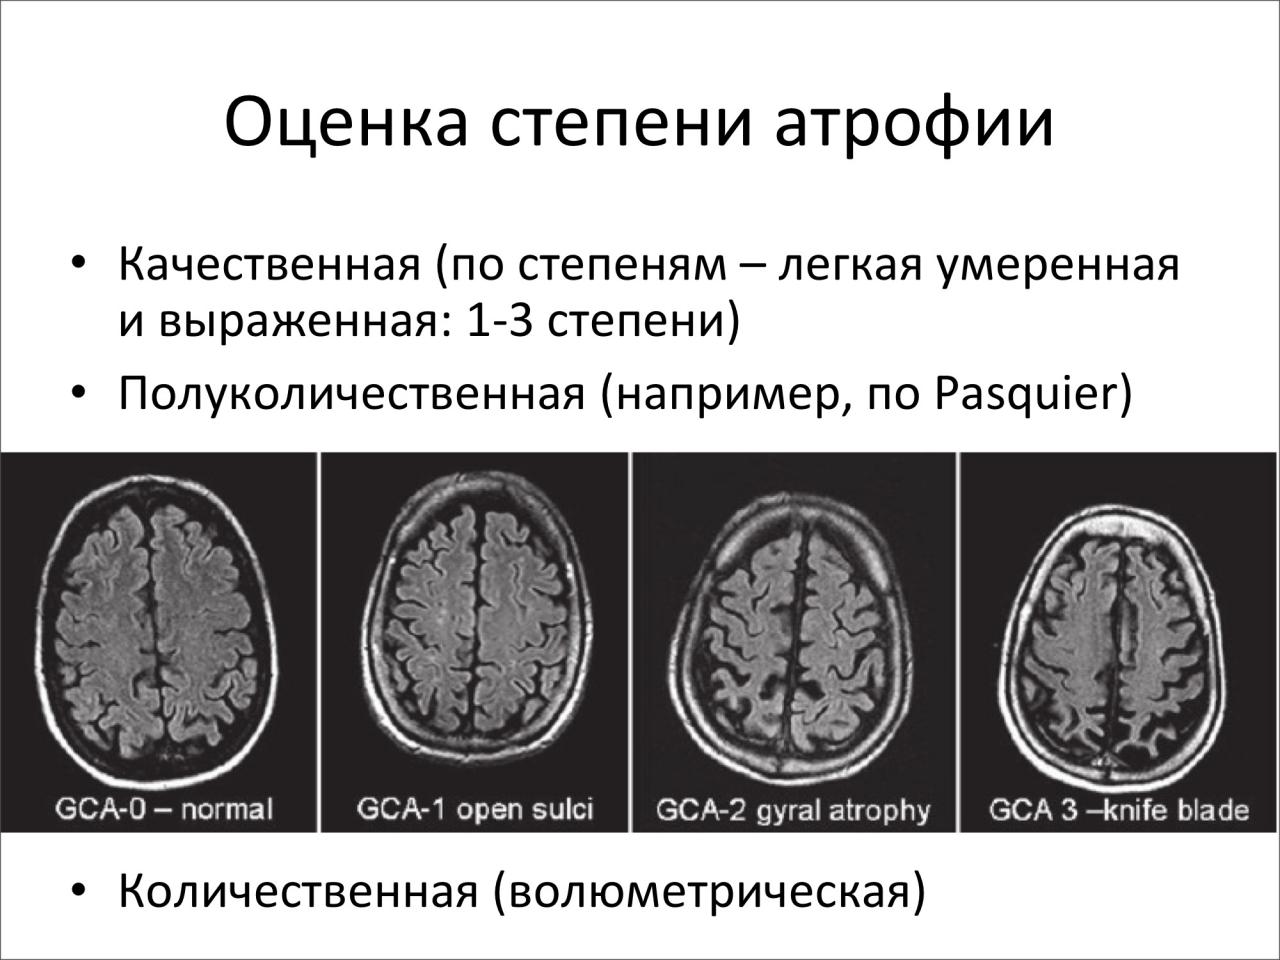

Признаки умеренно выраженной наружная

Признаки умеренно выраженной наружная 113 фото